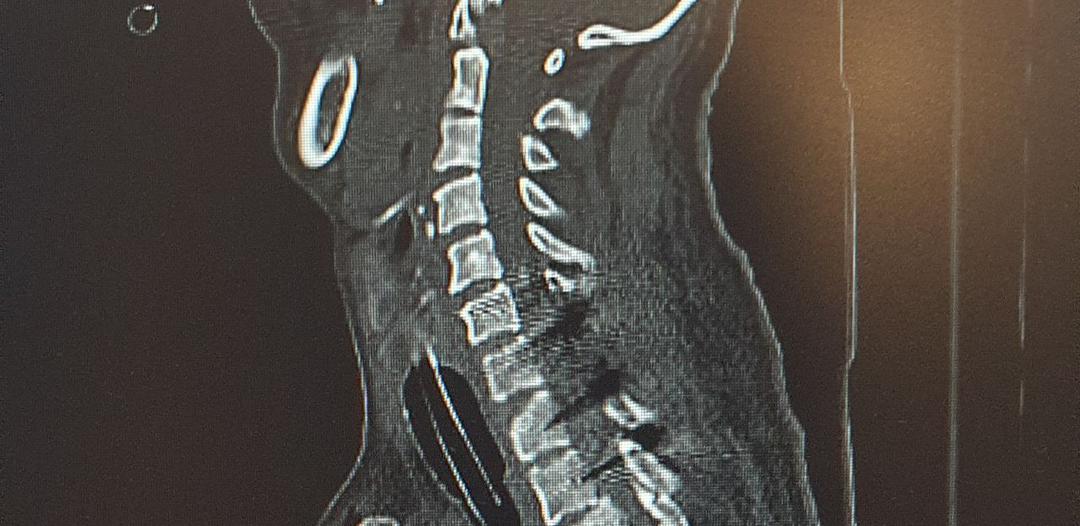

به گزارش روابط عمومی مرکز، این بیمار بر اثر سقوط از ارتفاع حدود ۶ متر دچار آسیبهای شدید در ناحیۀ سر، گردن و ستون فقرات پشتی شده بود. بر اساس گزارش تیم درمان، وی با شکستگی و دررفتگی مهره هفتم گردن (C7) و مهره اول پشتی (T1) به مرکز درمانی منتقل شد و در زمان پذیرش دچار فلج اندامهای تحتانی، اختلالات حسی، کاهش قدرت دستها و مشکلات تنفسی بود.

با توجه به شرایط حاد بیمار، دکتر شکراله زندی متخصص جراحی مغز و اعصاب اقدام به انجام جراحی بسیار پیچیده شامل وسیلهگذاری پدیکولار در مهرههایC6، C7، T1 و T2 کرد. این عمل بهدلیل حساسیت بالا در ناحیه گردنی- پشتی و وجود آسیبهای شدید، یکی از دشوارترین جراحیهای ستون فقرات محسوب میشود.